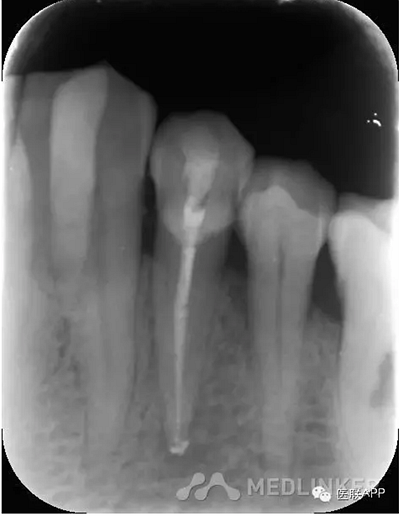

復診:去暫封,超聲蕩洗,干燥,試尖可,糊劑+熱牙膠根充,玻璃離子暫封,3月后復診,囑勿用患牙咬硬物。